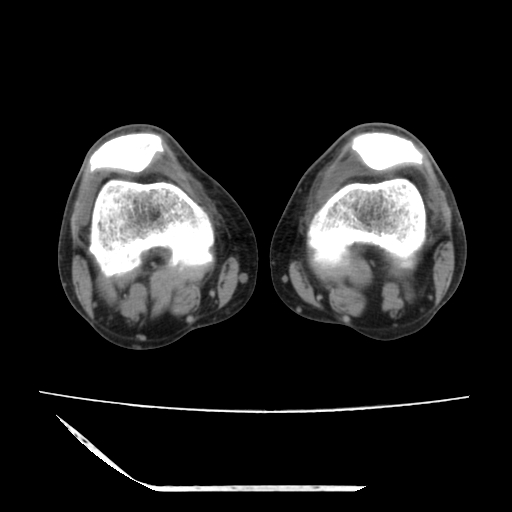

标题: CT13225:老年男性,左膝关节疼痛数月;请各位老师讨论。 [打印本页]

标题: CT13225:老年男性,左膝关节疼痛数月;请各位老师讨论。

骨质增生,骨性关节面硬化,关节积液,考虑退行性骨关节病

关节腔内少量积液,关节面退变。

双膝退变

骨质增生,骨性关节面硬化,关节间隙失常,关节积液,考虑退行性骨关节病.

骨质增生,骨性关节面硬化,关节积液,考虑退行性骨关节病。

这个病例诊断:退行性骨关节炎